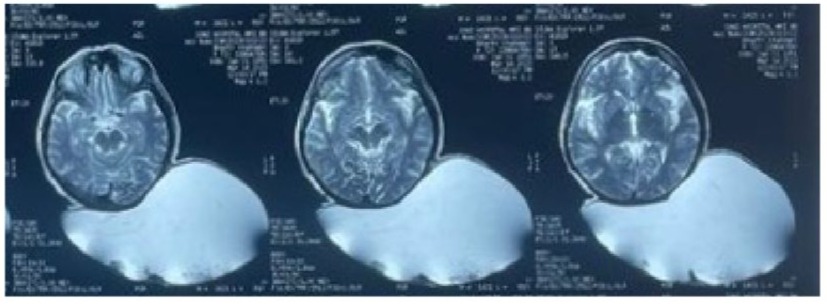

The patient was diagnosed with a large epidermoid cyst based on the findings. Lipoma and dermoid cyst were also considered as potential differential diagnoses. A preoperative Non-Contrast-CT scan of the skull was done to check for any bony or intracranial involvement. The scan revealed a large multiloculated, thin-walled, cystic fluid collection measuring 26 x 24 x 12 cm. The cyst was found in the deep scalp layers of the left parieto-occipital region and extended from the midline posterior high parietal region up to the posterior aspect of the occipital bone, abutting their outer cortices, with normal underlying bone with no intracranial extension of the lesion.On preoperative Magnetic Resonance Imaging (MRI), a large cystic lesion was detected in the scalp region between the parietal and occipital lobes. The lesion was well-defined, had multiple compartments, and measured around 26 cm × 24 cm × 12 cm. The cystic lesion did not affect the skull or brain. On T2-weighted images, the lesion appeared homogeneous with a high-intensity signal (Figure 3).

Figure 3 : T2 WI-Magnetic resonance image-Axial cuts.